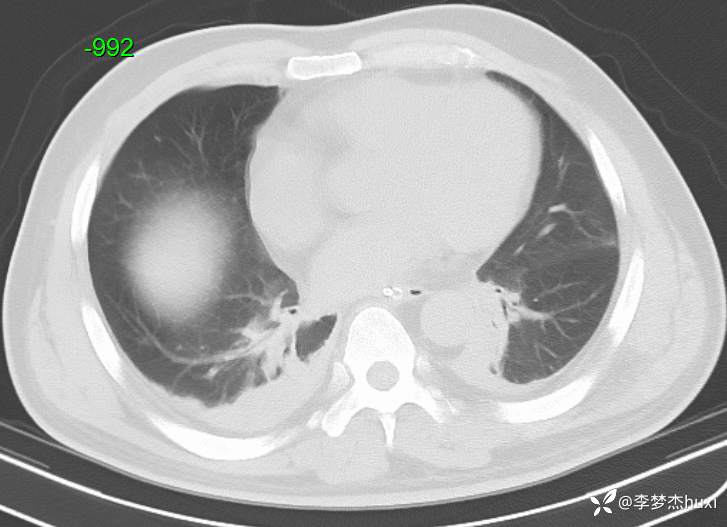

【现病史及既往史】: 1.现病史:患者老年 男,于入院前1天,患者在骑自行车时发生车祸,致伤头部,右颞顶部受力,伤后患者意识不清,右侧外耳道及右侧鼻腔出血,院外未处理,急来我院急诊就诊,查头颅CT示:右侧额颞顶枕部硬膜下血肿,颅内积气,蛛网膜下腔出血,左侧额颞部硬膜下出血?脑干密度减低,右侧颞顶部头皮软组织肿胀,右侧颞、顶骨骨折,右侧乳突小房密度增高。右侧外耳道密度增高。右侧蝶窦密度增高。胸部CT+三维重建示:双肺索条,双肺透过度欠均匀,双肺纹理增重,主动脉钙化,冠状动脉钙化。急诊以“闭合性颅脑损伤重型”收入我科。

【治疗经过及结果】:辅助检查:查头颅CT示:右侧额颞顶枕部硬膜下血肿,颅内积气,蛛网膜下腔出血,左侧额颞部硬膜下出血?脑干密度减低,右侧颞顶部头皮软组织肿胀,右侧颞、顶骨骨折,右侧乳突小房密度增高。右侧外耳道密度增高。右侧蝶窦密度增高。胸部CT+三维重建示:双肺索条,双肺透过度欠均匀,双肺纹理增重,主动脉钙化,冠状动脉钙化。

入院发生肺炎,猜病原菌